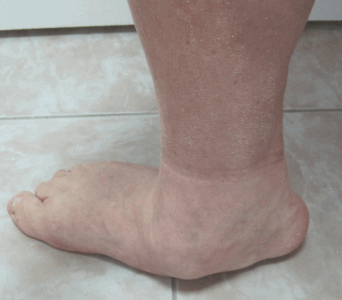

- Артроскопия голеностопного сустава. Показаний для операций на голеностопе очень много, делают её быстро и безболезненно. Реабилитация проходит в щадящем режиме, и в среднем через 5 недель пациент уже может спокойно ходить, полностью опираясь на стопу.

Данная операция приводит к инвалидности - кости скрепляются, формируется жёсткое межкостное соединение. Этот хирургический метод назначается при невозможности проведения более современной операции - артропластики. Обездвиживание некоторых суставов не вызывает ощутимого дискомфорта - при операции на подтаранном суставе пациент быстрее адаптируется, чем при артродезе голеностопа, где человеку придётся долго учиться ходить по новым правилам.

Артродез подтаранного сустава - самый простой по технике выполнения. Используется внутрисуставной метод с применением аутотрансплантата. Во время операции через заднебоковые области вводится специальное вещество, которое образует вокруг сустава небольшую полость, удобную для операции. Затем делаются небольшие надрезы, удаляется хрящевая прослойка, куда помещается трансплантат.